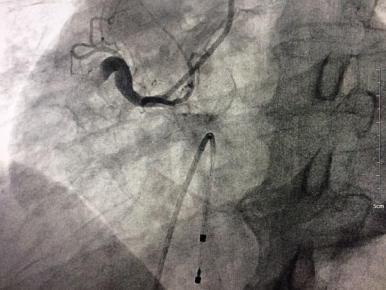

術(shù)前右冠動脈近段完全閉塞

????手術(shù)臺上,老人心率進行性下降到40次/分左右,病情極其危重。心內(nèi)科介入手術(shù)團隊迅速為患者植入心臟臨時起搏器,在臨時起搏器的保護下,醫(yī)生從血管穿刺開始僅耗時15分鐘就完成了冠脈造影術(shù),但檢查結(jié)果十分不樂觀:右冠狀動脈自近端完全閉塞,可見血栓影,袁小蓉立即采用特殊的藥物替羅非班注射液10ml在冠脈內(nèi)推注。在數(shù)分鐘內(nèi),醫(yī)生迅速、準確的為將導(dǎo)絲通過閉塞段,采用血栓抽吸導(dǎo)管進行血栓抽吸,植入支架,打通右冠狀動脈血管,手術(shù)成功了!

術(shù)后右冠動脈近端完全開通